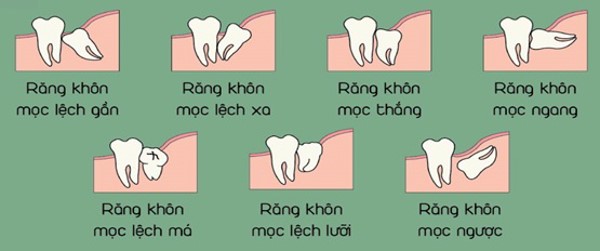

Răng số 8, còn được gọi là răng khôn, là những chiếc răng cuối cùng mọc trong khoang miệng, thường xuất hiện khi chúng ta ở độ tuổi từ 17 đến 25. Răng khôn có thể mọc thẳng hàng hoặc mọc lệch, mọc ngầm, thậm chí là không mọc lên được. Việc nhổ răng số 8 thường là giải pháp cuối cùng, được thực hiện khi răng khôn gây ra các vấn đề về sức khỏe răng miệng. Bài viết này sẽ cung cấp thông tin chi tiết về chi phí nhổ răng số 8, các yếu tố ảnh hưởng đến chi phí, quy trình nhổ răng, cũng như các thông tin bổ ích khác để bạn có thể đưa ra quyết định đúng đắn cho tình trạng răng miệng của mình.

Nguyên nhân răng số 8 mọc lệch, mọc ngầm

- Hàm không đủ chỗ: Hàm răng phát triển đầy đủ trước khi răng khôn mọc, dẫn đến việc không đủ chỗ cho chúng mọc lên một cách thẳng hàng.

- Bệnh lý răng miệng: Một số bệnh lý như xương hàm phát triển bất thường cũng có thể ảnh hưởng đến vị trí mọc của răng khôn.

- Răng mọc lệch, mọc ngầm: Gây ảnh hưởng đến các răng kế cận, gây đau nhức, viêm nướu, khó vệ sinh răng miệng.

Mức độ lệch của răng số 8 có thể ảnh hưởng đến chi phí nhổ răng. Nếu răng bị lệch nghiêng, việc nhổ răng sẽ phức tạp hơn và đòi hỏi kỹ thuật cao hơn từ phía nha sĩ. Do đó, việc điều chỉnh mức độ lệch của răng có thể tăng chi phí nhổ răng số 8.

Vấn đề răng mọc ngầm

Răng số 8 mọc ngầm dưới nướu cũng là một yếu tố ảnh hưởng đến chi phí nhổ răng. Việc phải thực hiện phẫu thuật để lấy răng mọc ngầm có thể làm tăng chi phí và đòi hỏi thời gian và công sức lớn hơn từ phía nha sĩ.